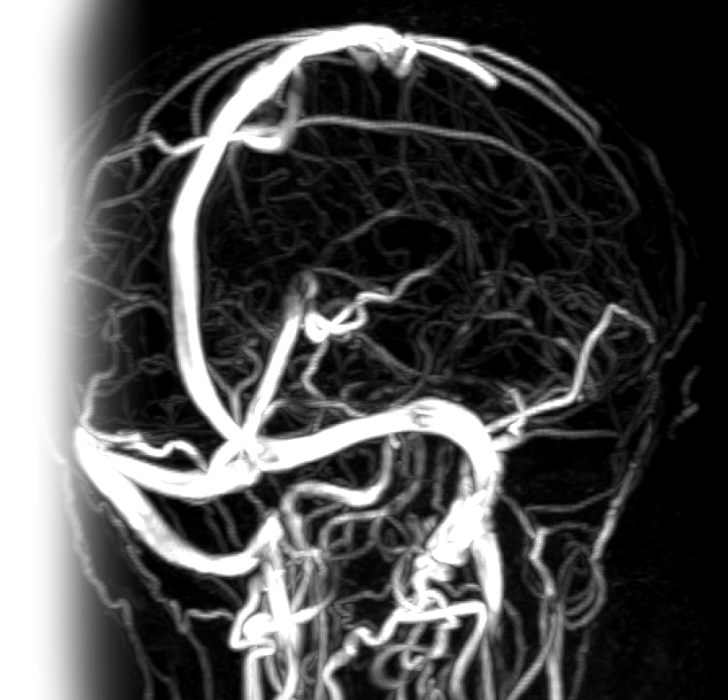

МР бесконтрастная венография интракраниальных вен и синусов МР бесконтрастная венография интракраниальных вен и синусов

МР бесконтрастная венография интракраниальных вен и синусов

МР бесконтрастная венография интракраниальных вен и синусов – важный метод исследования, который позволяет оценить состояние вен и венозных синусов головного мозга.